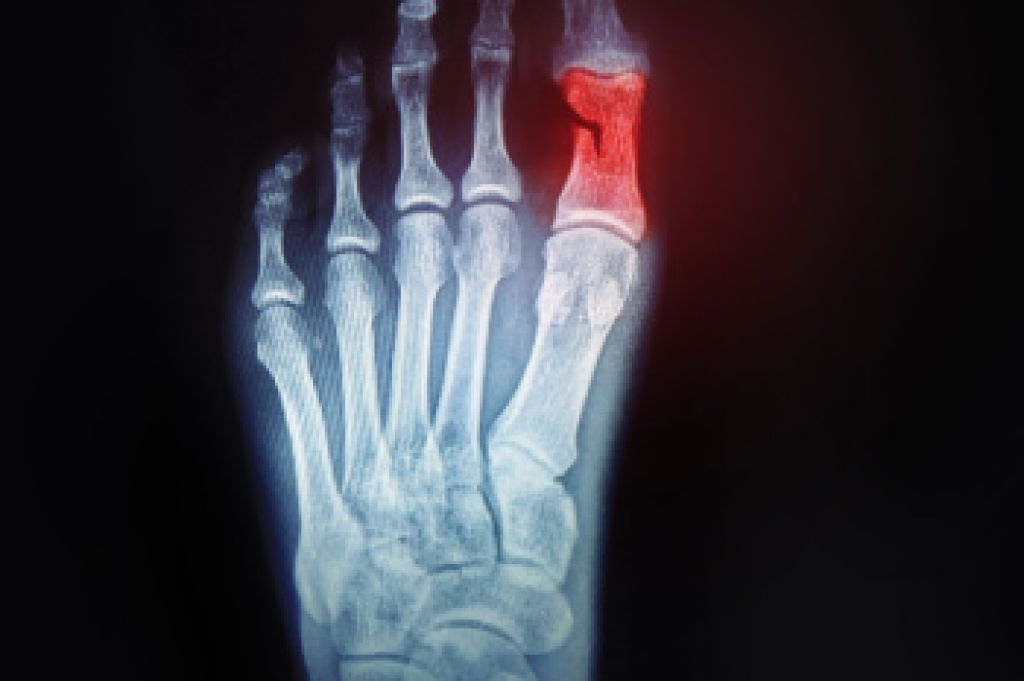

A broken toe occurs when one of the toe bones fractures due to trauma, stubbing, or dropping a heavy object on it. Causes include sports injuries, accidents, or repetitive stress. Risk factors are osteoporosis, poor footwear, and high impact activities. Symptoms may include swelling, bruising, and difficulty walking. Taping can help stabilize the toe if the break is minor, determined by evaluating pain, alignment, and mobility. The process involves gently wrapping the injured toe to its neighbor for support while avoiding circulation issues. A podiatrist can confirm the diagnosis, and provide treatment, which may or may not include buddy taping. If you suspect you have broken your pinky toe, it is strongly suggested that you promptly consult a podiatrist who can accurately diagnose the injury and offer the best treatment solution, preventing long-term complications.

A broken toe can be very painful and lead to complications if not properly fixed. If you have any concerns about your feet, contact one of our podiatrists from Redwood Podiatry Group. Our doctors will treat your foot and ankle needs.

What to Know About a Broken Toe

Although most people try to avoid foot trauma such as banging, stubbing, or dropping heavy objects on their feet, the unfortunate fact is that it is a common occurrence. Given the fact that toes are positioned in front of the feet, they typically sustain the brunt of such trauma. When trauma occurs to a toe, the result can be a painful break (fracture).

Symptoms of a Broken Toe

Generally, it is best to stay off of the injured toe with the affected foot elevated.

Severe toe fractures may be treated with a splint, cast, and in some cases, minor surgery. Due to its position and the pressure it endures with daily activity, future complications can occur if the big toe is not properly treated.